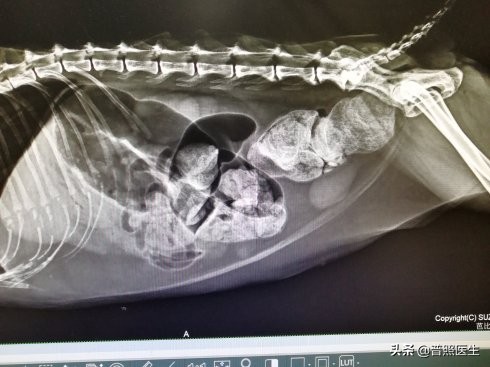

便秘在X光下是什么样子?

只能找张猫便秘的X光给大伙看看,人类的也是这样子。